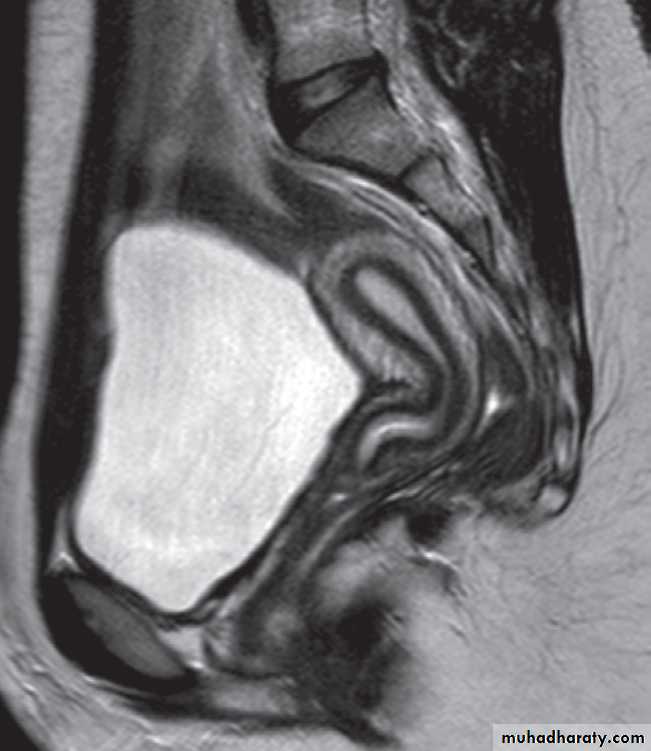

Magnetic resonance imagingPelvic anatomy is very well demonstrated because of the excellent soft tissue contrast afforded by MRI. Images are usually taken in the axial, coronal and sagittal planes . T2-weighted sagittal images show the vagina and cervix in continuity with the body of the uterus.

The zonal anatomy of the uterus is best demonstrated on T2-weighted images, with the endometrium having a high signal intensity, the adjacent inner myometrium (junctional zone) a low signal intensity, and the myometrium an intermediate signal intensity .

The cervix may be predominantly low in signal intensity.

Variations of uterine anatomy are well delineated on MRI-The ovaries are of intermediate signal intensity and often contain multiple high signal follicles on T2-weighted images

-The broad ligaments can also be identified in MRI